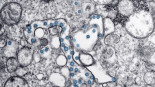

El CSIC obtiene un nanomaterial que elimina el coronavirus y puede aplicarse en mascarillas y tejidos

Un equipo de investigadores del Consejo Superior de Investigaciones Científicas (CSIC) ha desarrollado un nuevo nanomaterial, constituido por nanopartículas de cobre, que inhibe las proteínas del coronavirus SARS-CoV-2, causante de la Covid-19, y bloquea su propagación. El material, que ya ha sido protegido mediante patente, es aplicable en recubrimiento de mascarillas quirúrgicas, en tejidos de protección de uso hospitalario, y en recubrimiento de superficies de contacto, como barandillas o pomos en el transporte público.